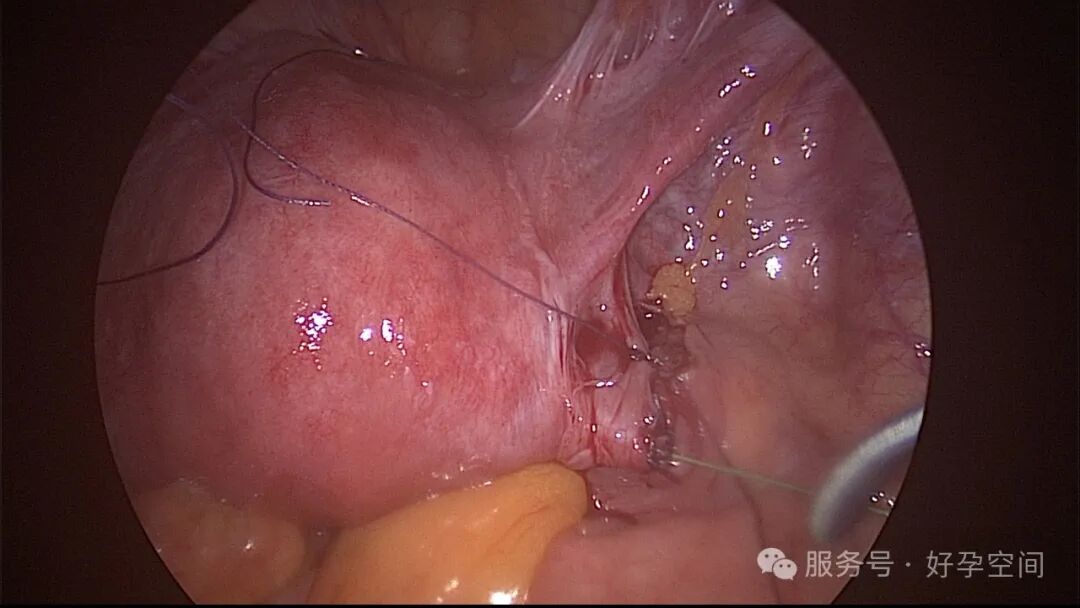

输卵管吻合术后妊娠,稽留流产,清宫术后宫腔粘连,宫腔镜单极电针分粘

分粘后宫腔镜二探,残留少许膜性粘连,镜鞘分粘